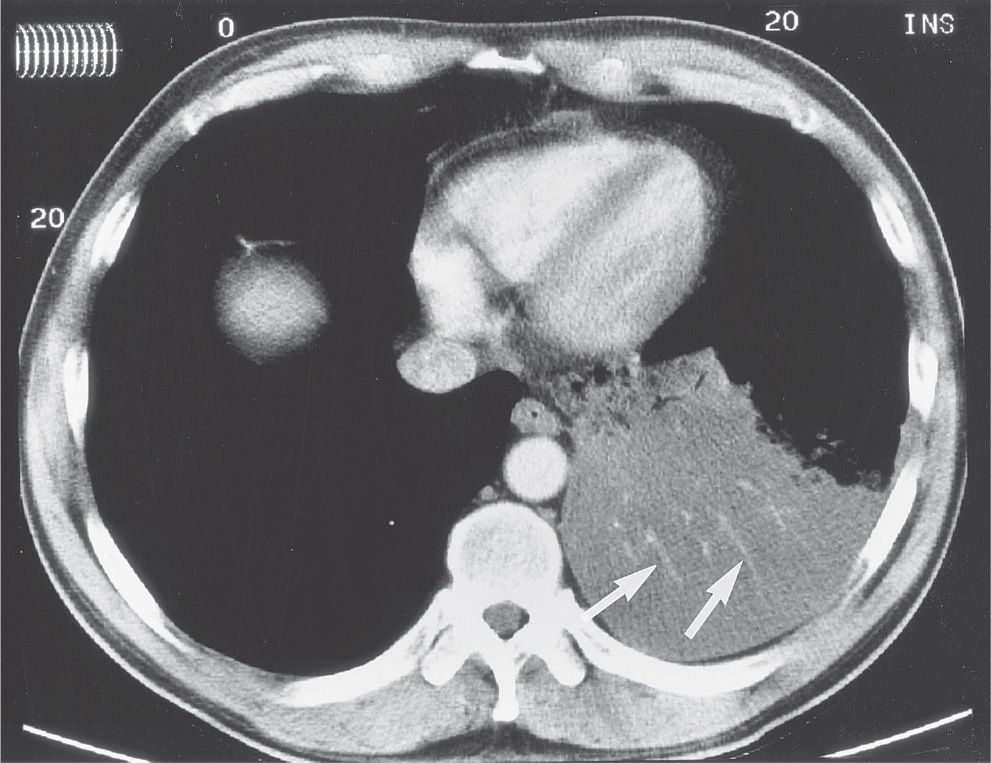

from radiologyassistant.nl